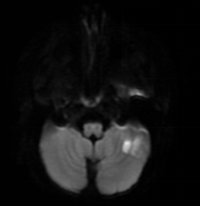

答:確診主要依靠頭顱磁共振檢查。引起兒童腦梗死的原因多樣,某些原因還會誘發(fā)腦梗死的復(fù)發(fā),因此對于腦梗死的患兒需進(jìn)一步評估有無心臟、血管及血液系統(tǒng)的其他危險因素。